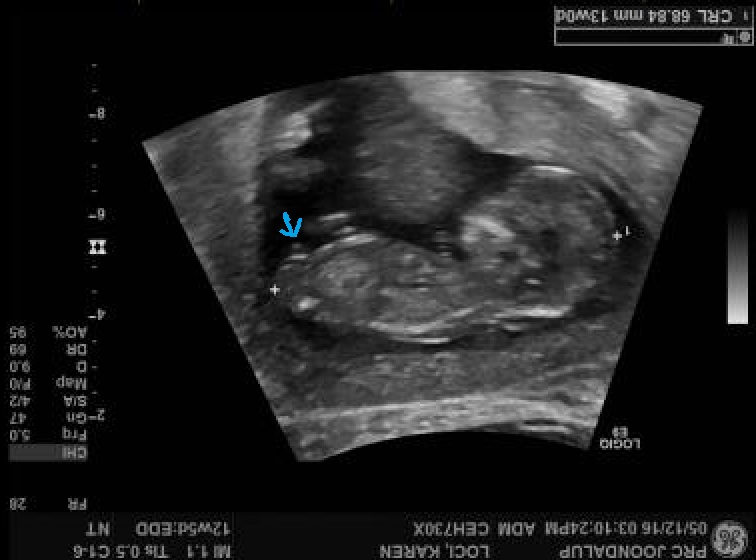

3rd,4th,5th and 6th are 12 week shots

and the two bottom shots are my two boys at 20 weeks. ( you can see that they have the same skull) but this current bub has different shape.